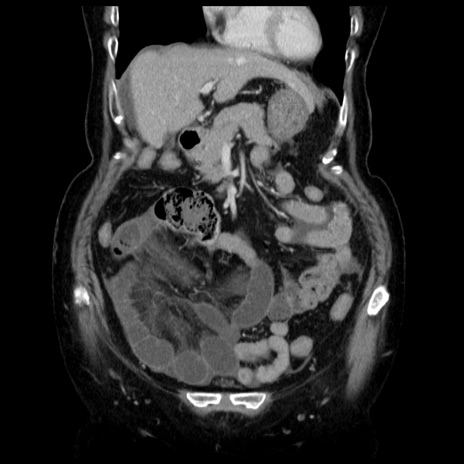

症例13(冠状断像)

【症例】70歳代女性

【主訴】腹痛、嘔吐

【現病歴】15時間程前(昨晩)より腹痛あり。今朝になっても症状の改善なく、嘔吐あり。腹痛も増悪あり、救急外来受診。

【既往歴】子宮癌全摘術後

【身体所見】意識清明、BP 121/72mmHg、P 74bpm、SpO2 100%(RA)、腹部:平坦・軟、腸雑音ほぼ聴取せず。下腹部・心窩部・臍左上に圧痛あり。反跳痛なし。

【データ】WBC 10600、CRP 0.15